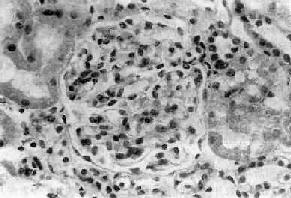

图12-12 新月体性肾小球肾炎

肾球囊壁层上皮细胞增生,其间有单核巨噬细胞浸润形成新月体,肾球囊腔被阻塞